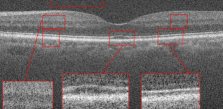

For testing the algorithm for the super-resolution of images of dataset3, 1 subject from each category has been selected and the algorithms have been applied for the super-resolution of artificially missed B-scans. Patch sizes were set equal to 5 and 7 with window size [2,2] and window size for MDT was set to [4,4] (recall that the window size for MDT has been selected for achieving the best output). The results have been presented in Fig. 7. Similar to the dataset2, in this dataset, no reference image is available and only visual comparison and CNR have been reported. CNR for each algorithm has been written beneath the resulting image. Visual comparison in addition to the resulting CNR’s, show the effectiveness of the proposed algorithm.

Original noisy image

Incomplete image

Spline interpolation

MDT [43]

Proposed algorithm

CNR = 1.3654

CNR = 0.2807

CNR=1.9968

CNR=2.0549

CNR=2.7711

CNR=1.493

CNR=0.2835

CNR=2.3996

CNR=2.2534

CNR=3.6184

CNR=1.1753

CNR=0.2446

CNR=1.7957

CNR=1.8335

CNR=2.1343